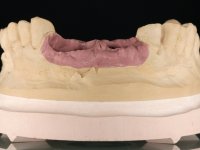

Segunda Fase

6 meses após a colocação da ponte, o paciente sofre um novo traumatismo comprometendo a viabilidade dos dentes 1.2 e 1.1. Foi realizada uma prótese removível acrílica para reabilitar provisoriamente o paciente enquanto foram extraídos os dentes 1.2 e 1.1 e foi colocado o implante no local do dente 1.1. Passados 3 meses foi realizada uma impressão ao implante colocado no 1.1 e simultaneamente foi feito um arrasto da ponte dos dentes 2.1 e 2.2. Para esse efeito no implante 2.1 foi utilizado um parafuso de uma peça de transferência. Dessa forma conseguiu-se impressionar corretamente a arquitetura gengival do sector antero-superior. O objetivo era simultaneamente impressionar corretamente esta zona e aproveitar a estrutura metálica desta ponte para confecionar a nova ponte de 4 elementos. Foi colocado um parafuso de cicatrização no implante 2.1 e foram acrescentados os dentes 2.1 e 2.2 na prótese removível. Com perícia laboratorial foi criada uma nova infraestrutura metálica de 4 elementos assente nos implantes 1.1 e 2.1 e com os elementos pônticos suspensos 1.2 e 2.2. No implante 2.1 manteve-se a conexão interna ao implante no implante 1.1 optou-se por uma peça intermédia facilitando a inserção da infraestrutura. A nova infraestrutura foi verificada em boca. Como pode ter havido alguma alteração da arquitetura gengival com a remoção da ponte e colocação do parafuso de cicatrização no 2.1, foi feita uma chave de silicone para permitir uma impressão de arrasto da infraestrutura metálica. Uma nova gengiva artificial foi realizada no modelo de trabalho de acordo com esta impressão de arrasto. Foi colocada cerâmica de tonalidade coronária e gengival. A peça protética foi aparafusada lentamente em boca para permitir uma adaptação dos tecidos moles. Após o correto assentamento e verificação imagiológica a ponte foi definitivamente apertada em boca e os orifícios de acesso obturados. Independentemente dos infortúnios que o paciente teve, pude ter a satisfação de o ver contente com esta reabilitação.